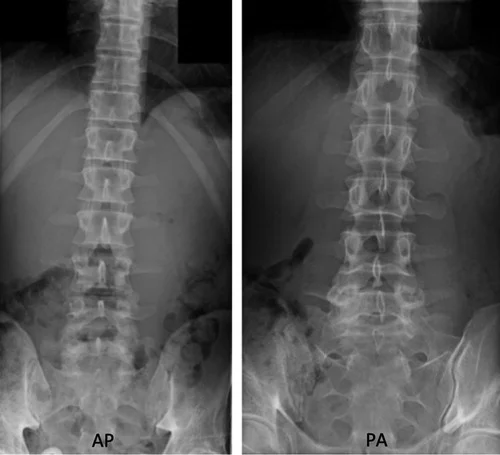

What is an X-ray Lumbar Spine AP & Lateral View Test?

X-Ray Lumbar Spine AP & LAT The view test was carried out to investigate the lower back region. This includes the lumbar spinal bones (L1 to L5), the intervertebral discs, and the surrounding muscles and other soft tissues.

This test is used to check for an injury to the spinal column's bones, determine the reason for the patient's lower back pain, diagnose any possible bone tumours, osteoarthritis, osteoporosis, or infections, and identify any possible disc abnormalities.